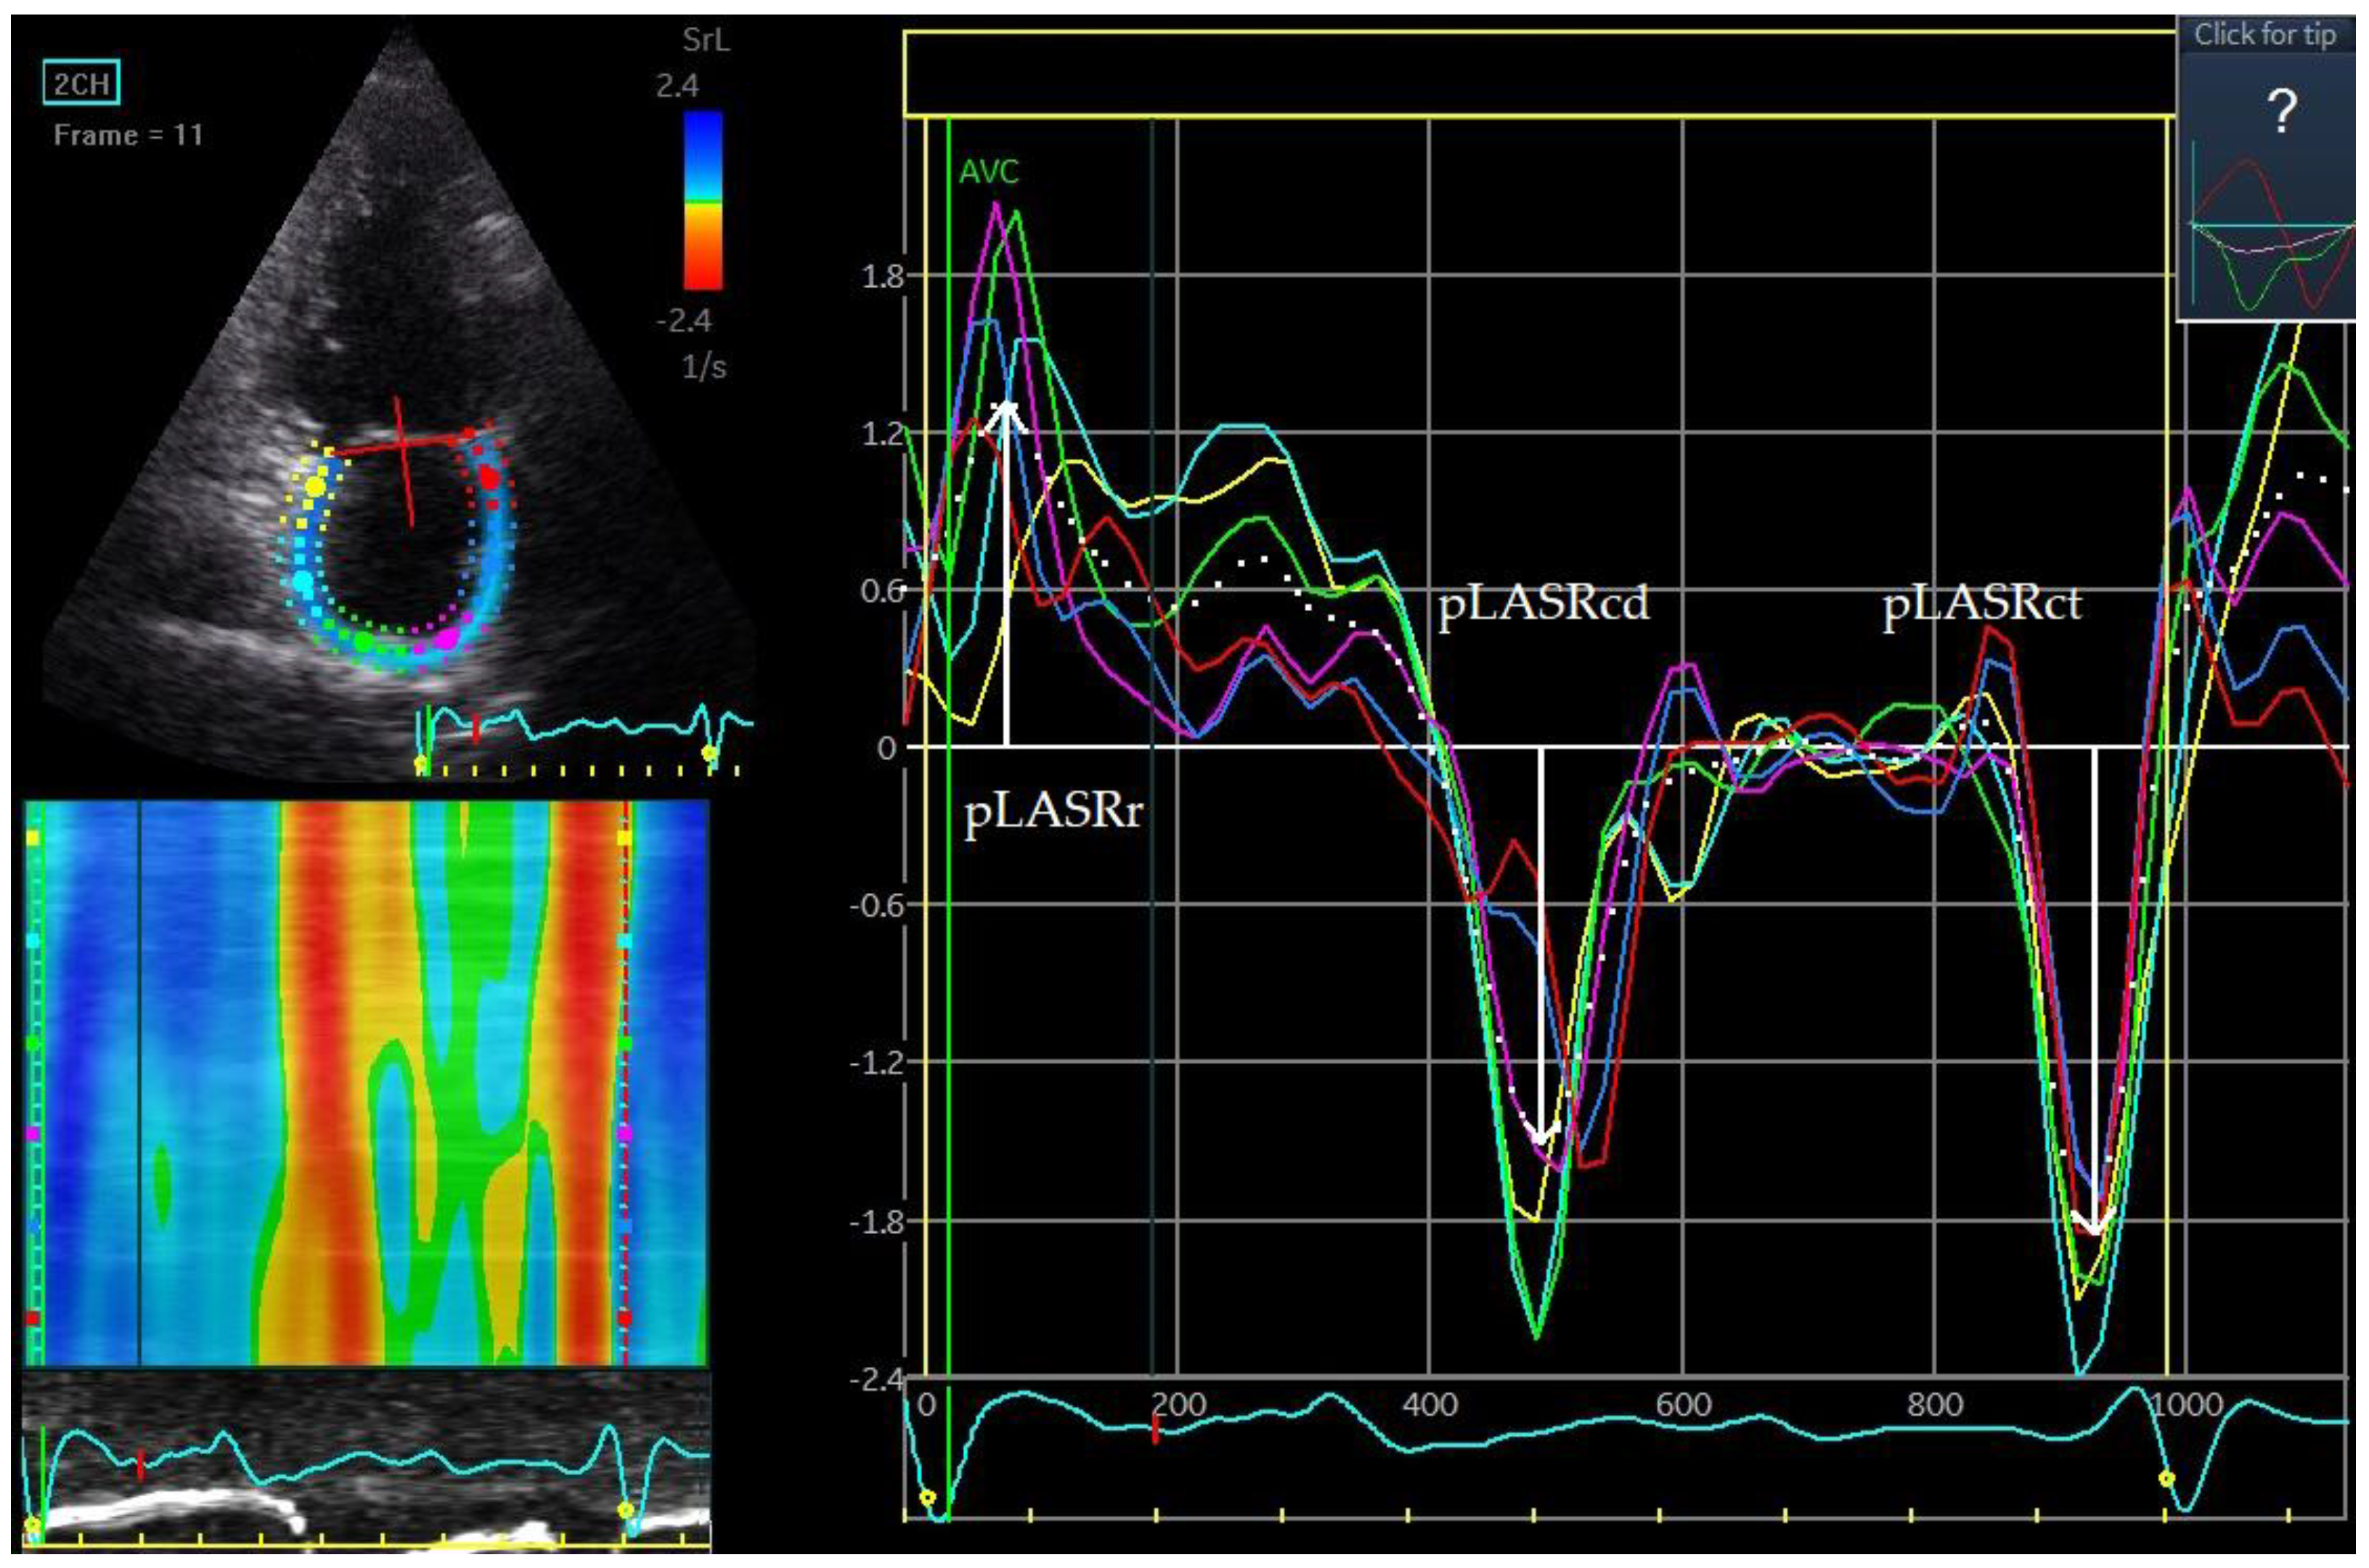

Figure 5. Left atrial strain rate. pLASRr 1.3 s−1 peak left atrial strain rate measured during the reservoir phase. pLASRcd −1.5 s−1, peak left atrial strain rate measured during the conduit phase. pLASRct −1.9 s−1, peak left atrial strain rate measured during the contractile phase. The measurements are the average of the 6 assessed left atrial wall segments. The measurement was made in the apical two-chamber projection during sinus rhythm.